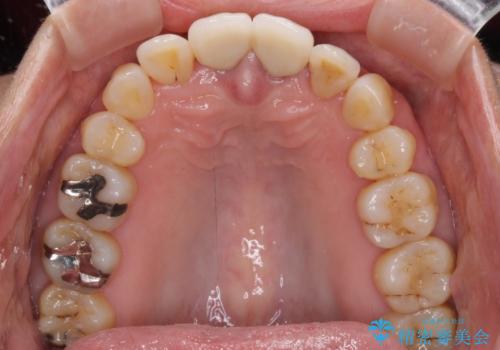

- 上の前歯の変色と、下の前歯のデコボコを気にして来院された患者様です。

前歯はオールセラミッククラウンに補綴することとしました。

当初は上顎の補綴治療のみを希望されていましたが、奥歯にブリッジなど補綴物が多くあり、前歯も変色しているため、治療費が高額となってしまうことが懸念されました。

相談の上、最も気になっている前歯の部分矯正と補綴治療により口元の改善を図ることとしました。

審美面と合わせて清掃性も改善され、患者様には大変満足していただきました。